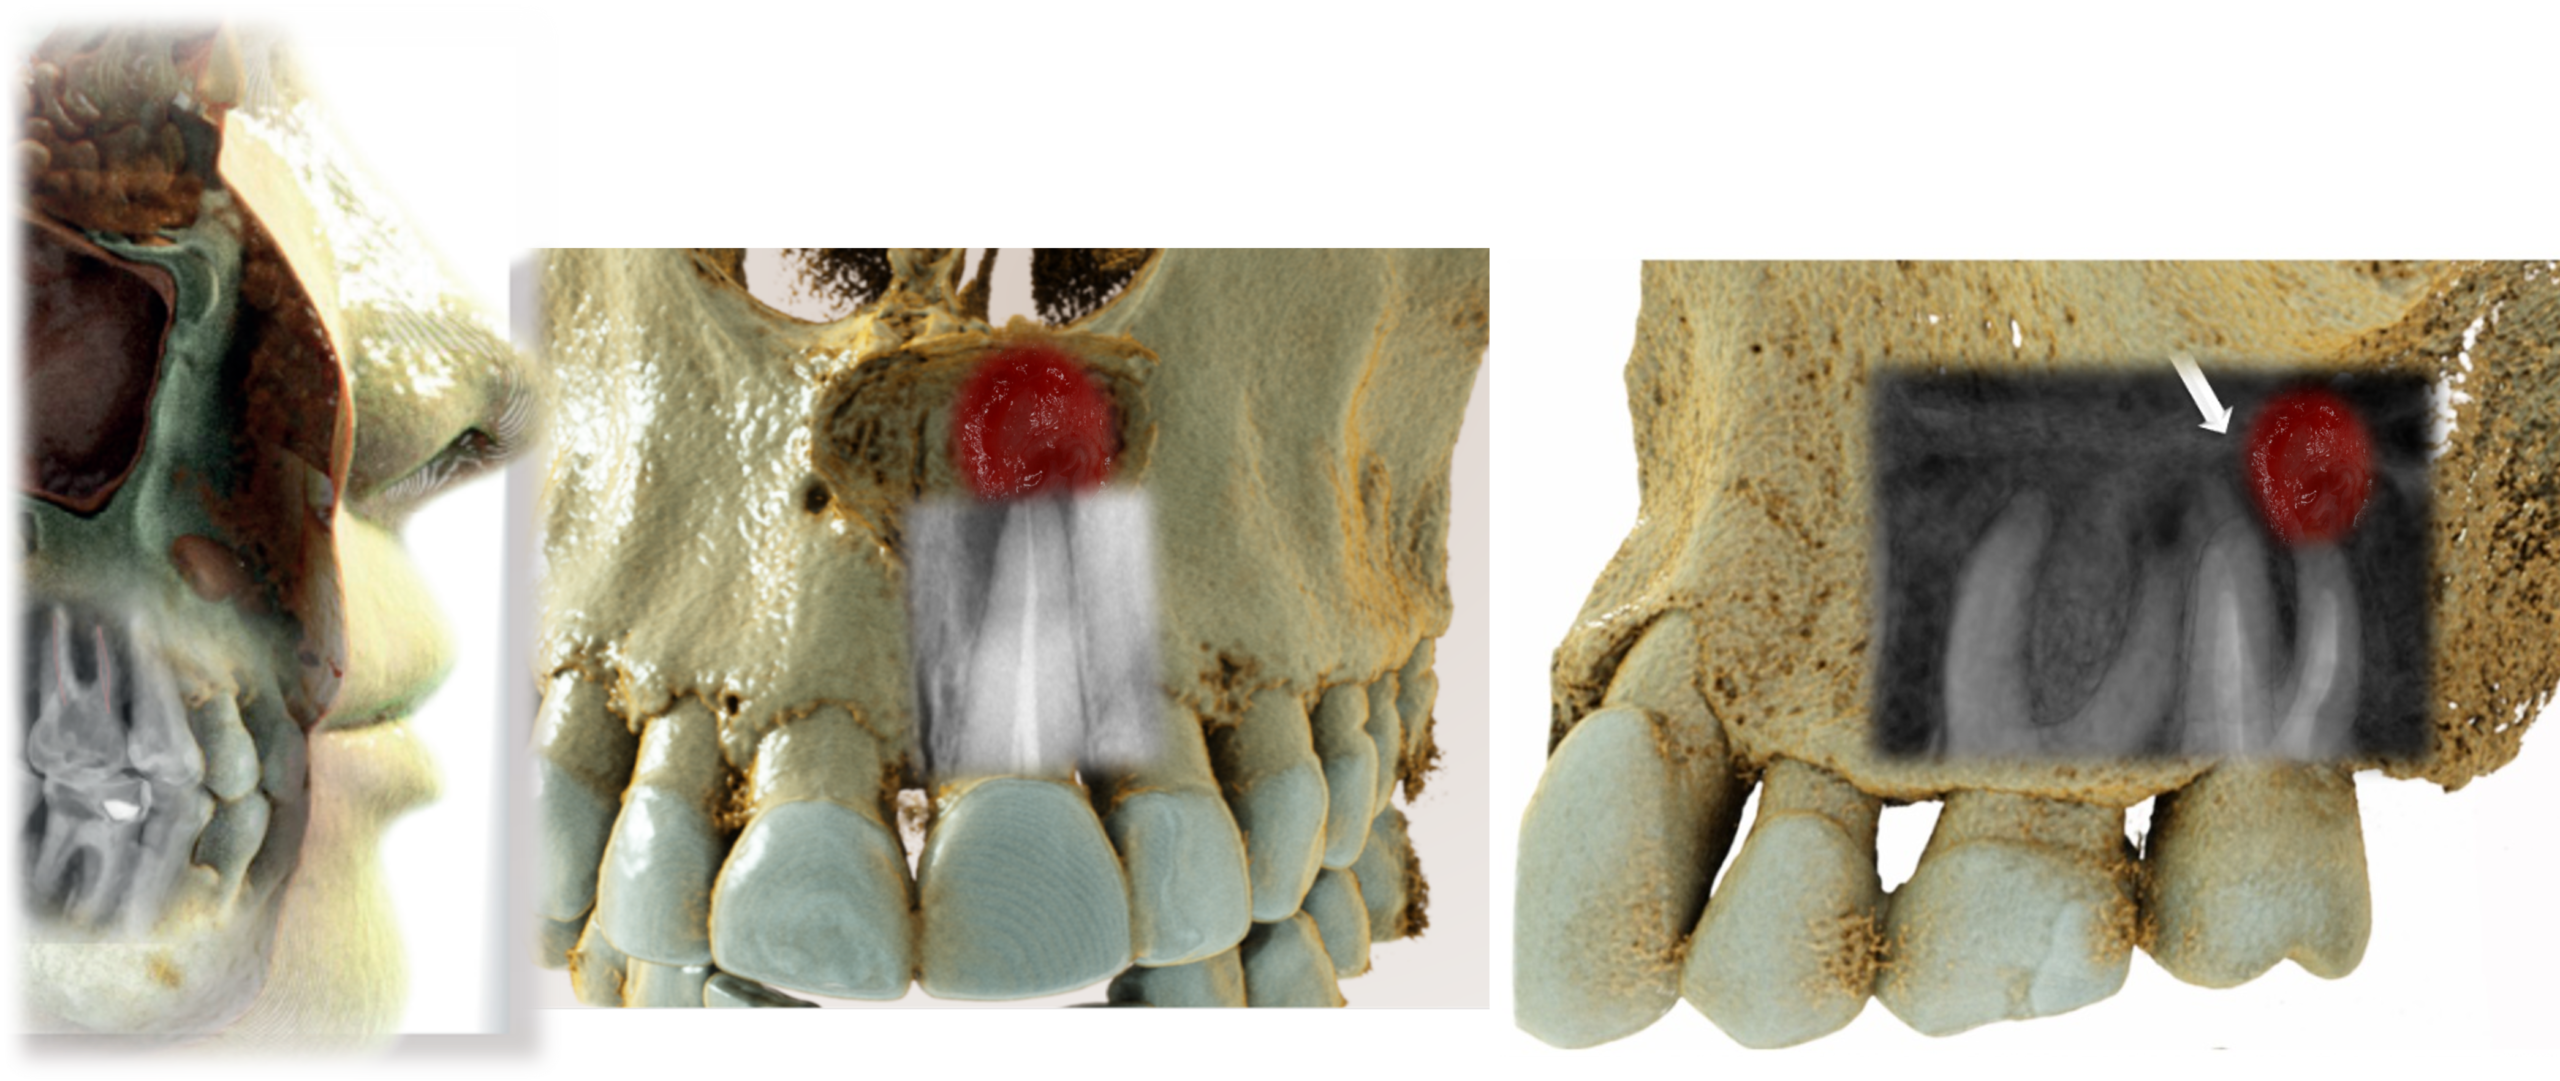

Hands-on training with AI tools to enhance and recolor CBCT data. Create hyper-realistic anatomical renderings using large language model software — images that educate patients and elevate your practice.

One of the most powerful skills you'll gain: using large language model software to transform raw CBCT data into stunning, clinically accurate anatomical renderings. These images revolutionize patient communication and case presentation.